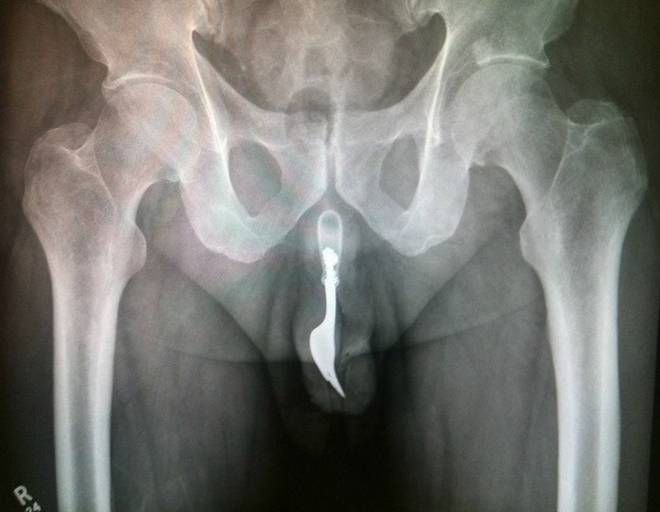

ROMA – Con il sesso i giochi erotici possono essere molto variegati. Questa “compilation” mostra però come a volte quei giochini finiscono male. Ecco infatti svariate radiografie eseguite negli ospedali di tutto il mondo.

Tutte queste persone sono state ricoverate con diversi oggetti incastrati nell’ano e non solo: dal cellulare alle chiavi di casa, passando per proiettili e giocattoli come macchinine e pupazzetti.

Anche il sex toy, a quanto pare deve essere usato responsabilmente. Specialmente quando l’oggetto è improvvisato. E chi rimane con l’oggetto incastrato cosa deve fare? Come spiegano i medici dei pronto soccorso, non bisogna provare a risolvere il problema da soli senza andare in ospedale. In molti casi infatti, alcune persone vengono ricoverate sia con l’oggetto, sia con le pinze utilizzate per recuperare l’oggetto, conficcate nell’ano.